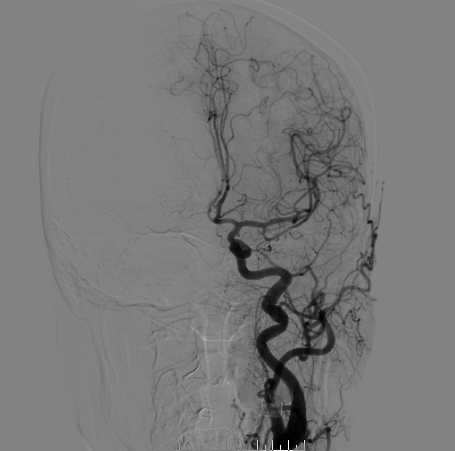

右侧颈总造影:右侧大脑中动脉瘤

右侧大脑中动脉瘤,瘤颈处发出颞支,颈宽3.79mm,瘤高3.51mm,远近端载瘤动脉直径分别为2.43mm、2.52mm。